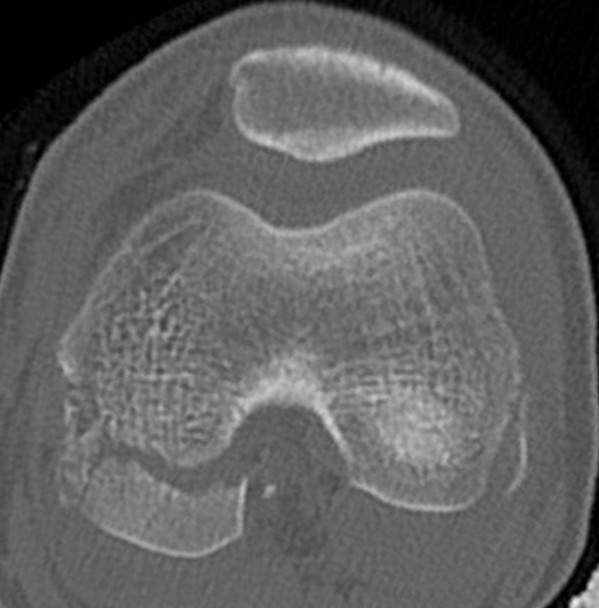

SH2Dis femurDis femur

Management

CT / MRI - assess percentage of bony bridge

Bony bridge < 50%

- excision and fat graft

- manage angular deformity with 8 plates / osteotomy

Bony bridge > 50%

- hemi-epiphysiodesis

- may need later correction of LLD and angular deformity